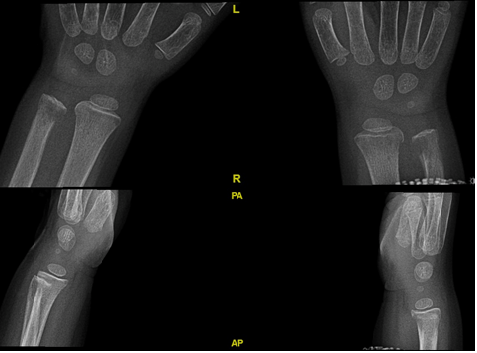

The radiographs bilateral ulnar symmetrical distal metaphyseal eccentric osteolytic lesions are seen with disruption of the medial cortex; however no periosteal reaction. Also, there is small osteolytic lesion within the distal radius (Figure 2). Both knees showed signs of osteopenia, the thick sclerotic metaphyseal line above a widened physis, and small beak-like excrescences at the metaphysis of both tibias (metaphyseal clefts). Ring of increased density surrounding epiphysis (Wimberger ring) (Figure 3). US guided aspiration of both knees show no signs of infection. MRI of wrist was done which show diffuse bilateral bone marrow oedema of the distal ulna and radius both sides. This is associated with evidence of diffuse periosteitis and soft tissue oedema however no apparent fluid collections. Subcutaneous oedema is also identified. No apparent acute fractures. No focal osseous lesions. Intact extensor and the flexor tendons bilaterally and bone: Generalized bone marrow oedema is seen more pronounced around the knee and wrist joints. (Figure 4).

Figure 2 Bilateral wrist x ray AP and lateral view show ulnar symmetrical distal metaphyseal eccentric osteolytic lesions and disruption of the medial cortex with small osteolytic lesion of distal radius.